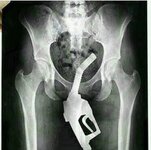

Resimde gördüğünüz şahıs benim ya da benim vücut ölçülerimdeki bir Fido da olabilir (Fido; Eski Fruko reklamlarındaki çizgi arkadaştır). Neyse şahıslara takılmadan aslı konumuza değinelim. İçinizden biri bana vücut ölçülerimizi elle girebileceğimiz bir program önermezse ikinci resimde yaptığıma benzer şeyler yapmaya devam edebilir ve hatta daha da ileri gidebilirim. Az önce yaz günü açık bırakılan camı fırsat bilerek eve giren 3 yarasayı evden çıkarmayı başardığıma göre daha bilimsel olarak bisikleti üreticinin verdiği ölçü bilgilerine göre çizmeye başlayabilirim. Bu saatte her ne delilikle uğraşıyorsanız sizlere de kolay gelsin.